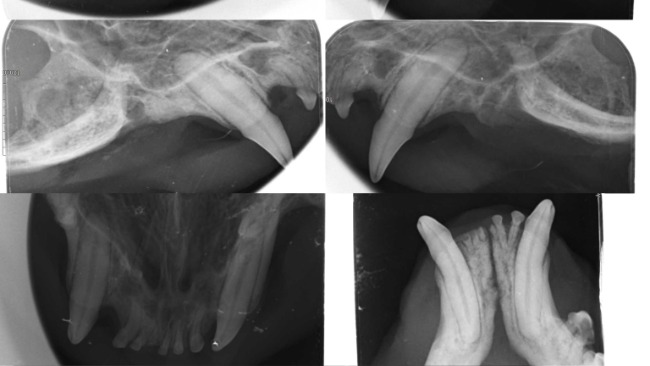

11/06-Został przeprowadzony zabieg stomatologiczny, zgodnie z założeniami Łobuz miał usunięte wszystkie zęby policzkowe oraz sieczne. Na RTG uzębienia uwidoczniono spory zanik kości zębodołu oraz liczne zmiany resorpcyjne (FORL). Od wczoraj dzięki Wam Łobuz się może cieszyć życiem bez bólu!!!